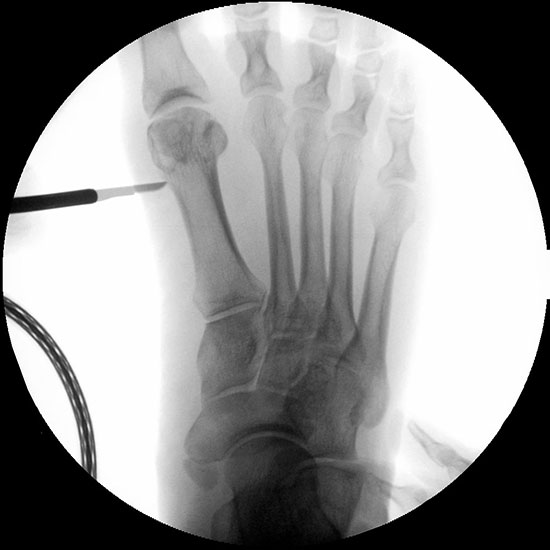

Abbildung 1

• Korrekturpotential größer als beim offenen Chevron, da die Gelenkkapsel als stabilisierendes Element erhalten bleibt und über eine trikortikale Osteosynthese mit zwei kanülierten Schrauben eine Verschiebung bis ca. 80% des Metatarsaledurchmessers möglich ist (Abb. 1).